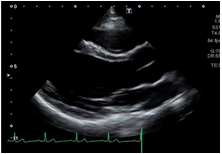

Adjustment of STC

STC, also known as TGC, is used to adjust to adjust the gain for depth-related attenuation in an image.